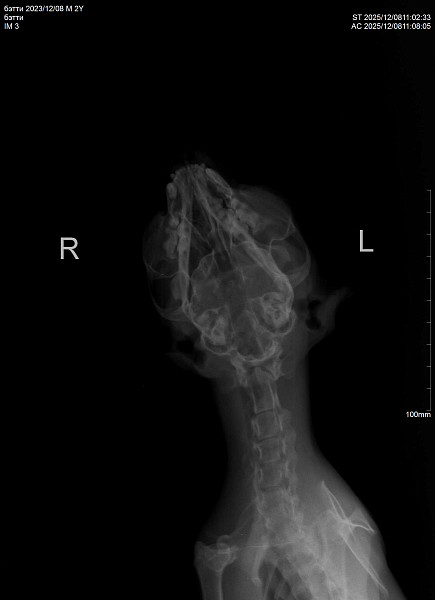

Здравствуйте! У нас кошка 10 дней находилась на улице. Через 10 дней вернулась никакая, сильное истощение, дезориентация. Кошка ходит и стукаетсях, как будто потеря в пространстве. Самостоятельно питаться не может. Повезли в ветеринарке, сделали рентген, говорят возможно ЧМТ или оттек головного мозга. Выписали препараты. Кормим со шприца, сейчас уже чуть бодрее стала, дней пять прошло после визита в ветеринару. Аппетит хороший. Но самостоятельно есть не может, зрительный рефлекс слабый. Глазки чистые.